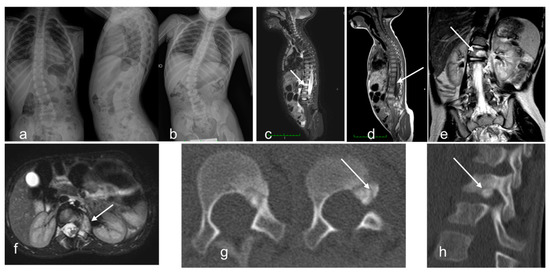

| 10 | F | 5 | pedicle L1, intra-articular cortical | back pain, scoliosis | yes | yes | no | - | yes | 2 | traumatic vertebral fracture | surgery resection |